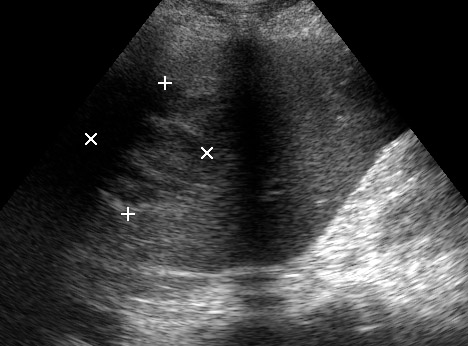

Типичная картина ##1-4:

Гипоэхогенное неоднородное округлое образование, окруженное эхогенным "демаркационным валом"

измененной паренхимы печени.

#5: Эмфизематозный абсцесс - в полости газ, экранирующий его содержимое.